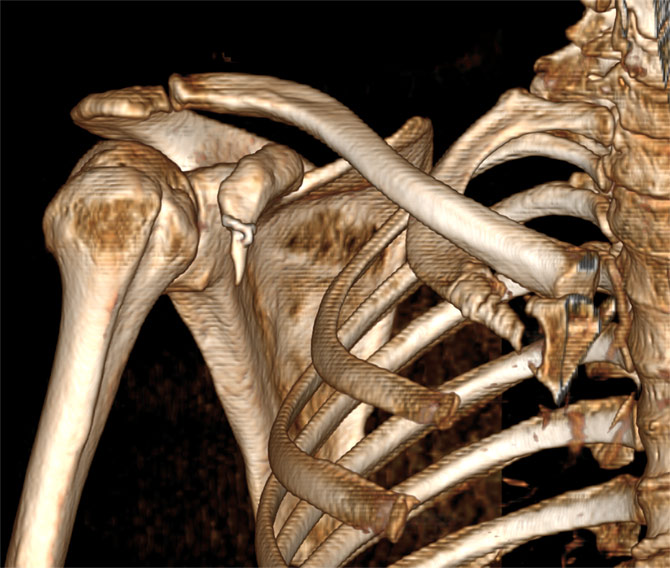

Reconstrucțiile se fac preferabil din secvențele cu fine (kernel de părți moi). Cele reconstruite din imaginile cu kernel de os sunt cu margini prea ascuțite.

Image

Reconstrucție tridimensională a oaselor din articulația umărului (VRT) din imaginile cu kernel de părți moi

Reconstrucție tridimensională a oaselor din articulația umărului (VRT) din imaginile cu kernel de os - contururi sharp